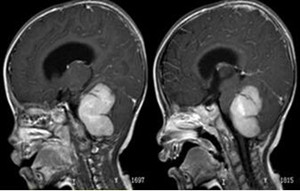

▲术前